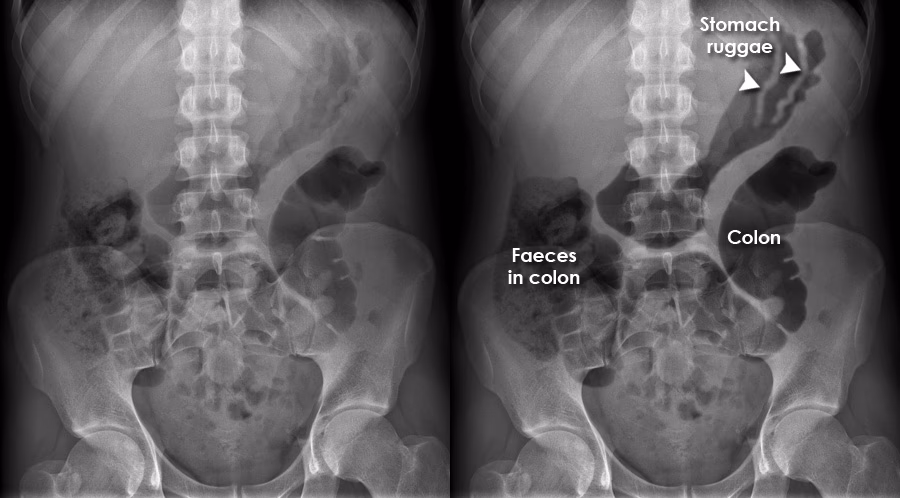

Nogle gange kan symptomer fra fordøjelsessystemet være misvisende. Et klassisk eksempel er "overløbsdiarré". En patient kan klage over diarré, men den underliggende årsag er faktisk alvorlig forstoppelse. Tilstanden opstår efter en lang periode med forstoppelse, hvor en hård, fast afføringsmasse (en fækalom) blokerer endetarmen. Denne blokering forhindrer normal afføring.

Kroppen reagerer på to måder: For det første får den udspilede endetarm den indre anale lukkemuskel til at slappe af. For det andet øger tyktarmen ovenfor blokeringen produktionen af væske og slim for at forsøge at opløse proppen. Denne blanding af væske, slim og små afføringspartikler siver derefter rundt om den hårde masse og ud af endetarmen. Patienten oplever dette som ukontrollerbar, vandig diarré, selvom det i virkeligheden er et tegn på en alvorlig forstoppelse, der kræver behandling.